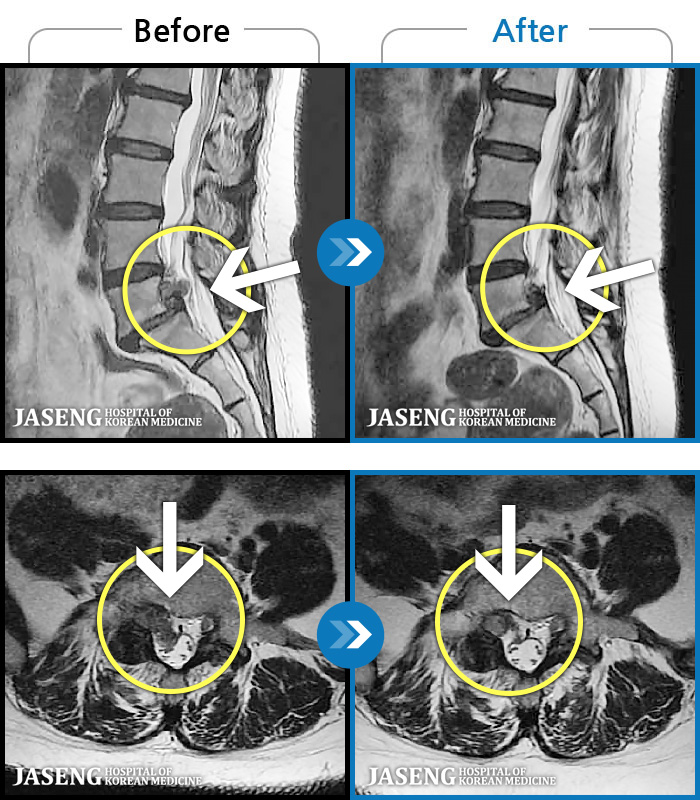

123 MRI ũ ʸ Ȯϼ.